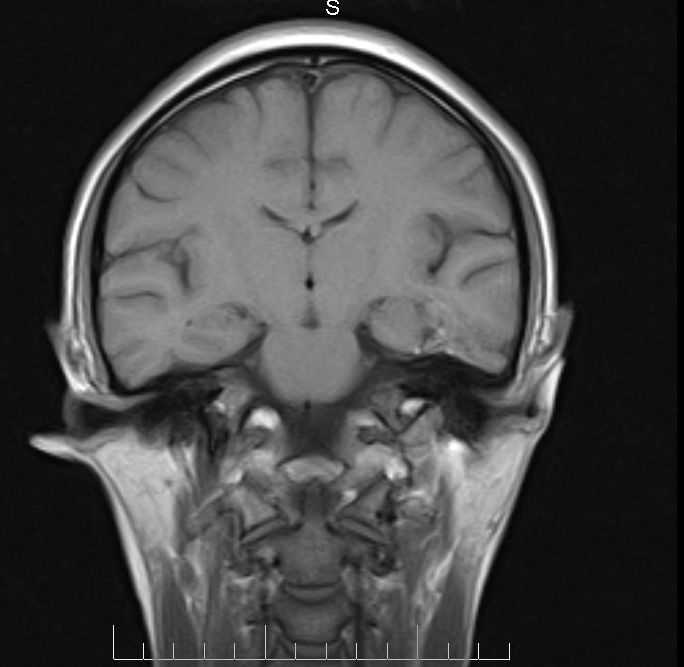

标题: MRI2379:30岁,男,癫痫10年,请各位看一下;CT示:左颞叶钙 [打印本页]

标题: MRI2379:30岁,男,癫痫10年,请各位看一下;CT示:左颞叶钙

左颞叶区见不规则点状混杂信号影

考虑血管畸形

支持2楼 左颞叶区见不规则点状混杂信号影,考虑动静脉畸形。

考虑左侧颞叶脑血管畸形(avm)。

考虑左侧颞叶脑血管畸形(avm)。----t1低等高混杂信号,t2等高信号周边较多流空血管影[冠状位明显],mra左侧大脑中动脉受压,远侧聚集.